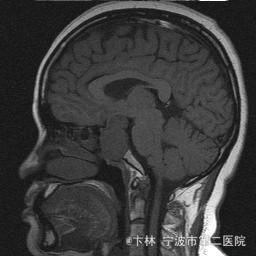

40岁女性,因“双眼视力下降三月余伴停经1个月余”入院。 患者三月前无明显诱因下出现双眼视力下降,视物模糊,尤以左眼为甚,只能近距离看到手动,无头痛、头晕,无恶心、呕吐,无视物旋转,无行走困难等不适,患者曾在某眼科医院就诊治疗,考虑为双眼视神经炎,予以营养,补液对症等治疗(具体不详),情况不见好转,近一月来患者月经停止,来我院神经外科门诊,予以查头颅CT,头颅MRI,提示“垂体大腺瘤”,为求进一步治疗收住入院

予以完善血,尿,粪常规检查,及凝血功能全套,输血功能全套及垂体功能全套,蝶鞍冠状CT等术前检查措施,行经蝶入路垂体瘤切除术。术后予以对症,补液,调节血电解质等治疗,患者视力明显改善,复查头颅MRI提示肿瘤基本全切,一周后患者出院。

此病人颅内垂体瘤体积较大,突破鞍隔压迫视交叉,故患者视力视野障碍为首发症状,该肿瘤主体有大部分向蝶窦腔生长,因此采用经蝶手术入路,肿瘤切除满意,术后患者视力视野恢复满意,。